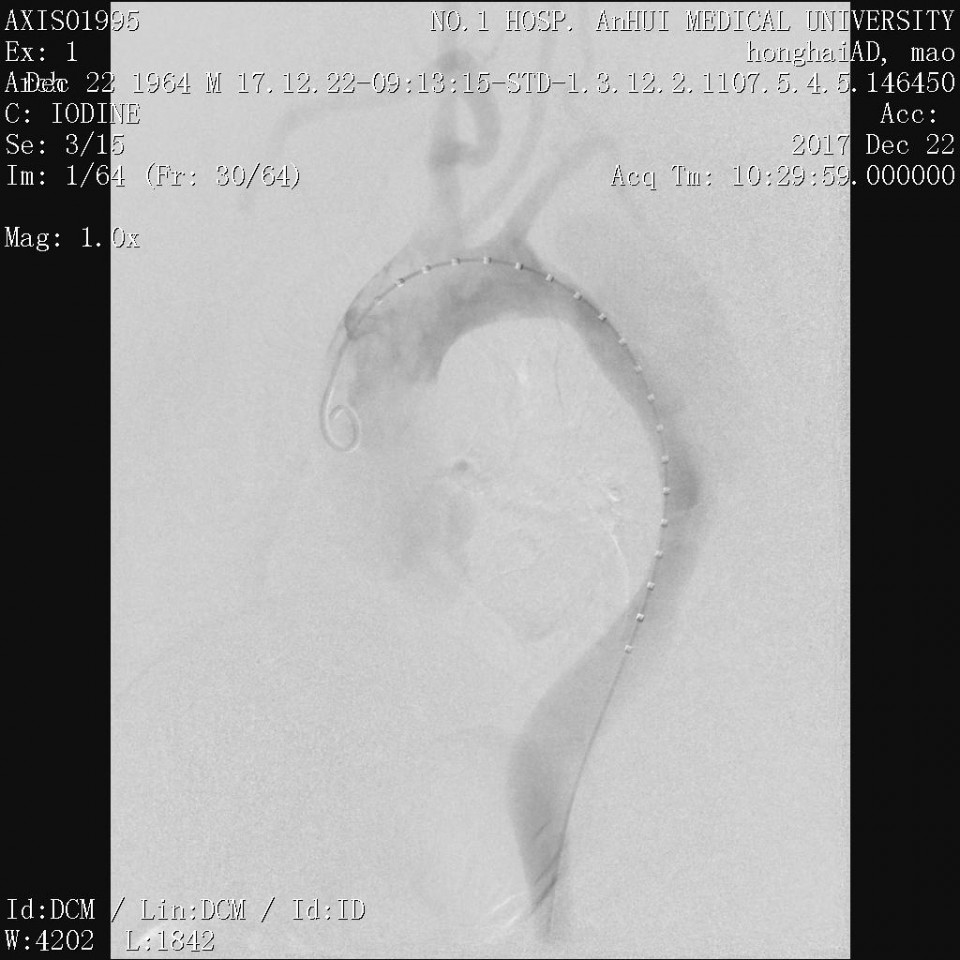

近日,我院血管外科成功应用Castor分支型支架(图1)治疗胸主动脉夹层一例,该病例为我省的首例植入。患者男性,53岁,因“突发胸痛2天”入院,既往有高血压病史。经CTA检查诊断为胸主动脉夹层,破口距离左锁骨下动脉(LSA)36mm,假腔逆撕至左锁LSA(图2、3)。既往一般选用直管型支架,需要部分或全部封闭LSA,但可能增加脑梗和截瘫风险。考虑到患者年龄较轻又是体力劳动者,经科室讨论决定使用Castor一体式分支型覆膜支架,一方面通过增加健康锚定区 (LCCA-LSA距离+LSA直径),进一步降低支架对于血管壁的刺激,从而降低夹层逆撕的风险;另一方面重建LSA保留功能,且不影响LCCA血流。 整个手术过程顺利,最后造影:Castor分支型支架定位精准,无移位;支架近端三重小波段密封性能良好,无内漏,破口被完全封堵,真腔被打开;LSA及LCCA血流通畅,手术圆满成功。病人术后恢复良好(图4、5、6)。